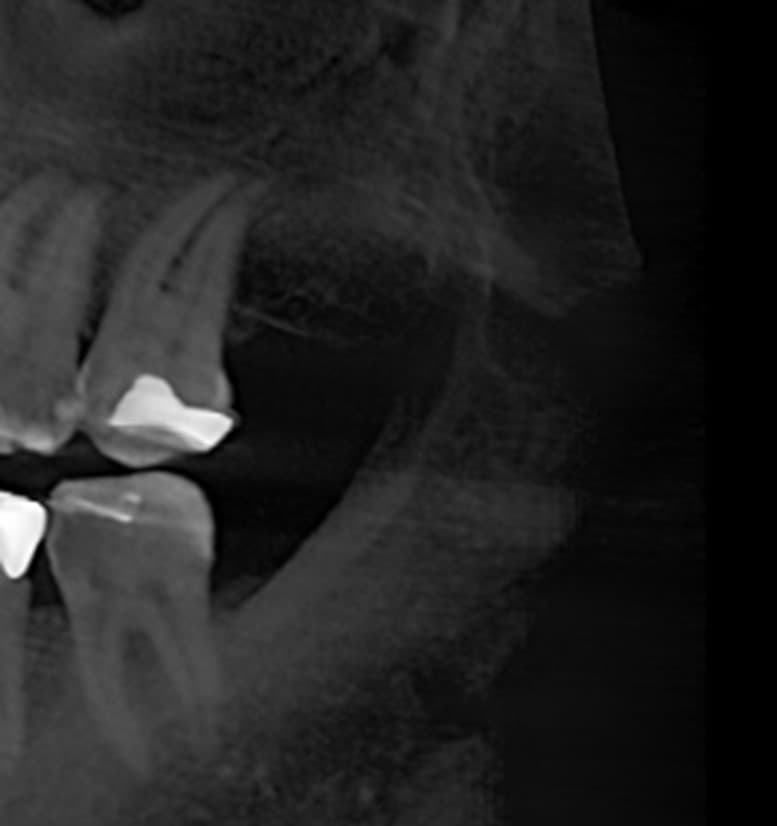

Diagnosis often involves advanced imaging techniques like cone beam computed tomography (CBCT), enabling precise identification and assessment of these cavitations. Early detection and appropriate treatment are crucial for preventing further complications and restoring dental health.

Our clinic offers advanced solutions utilizing Cone Beam tomography technology, the most widely used in the United States. This approach allows us to detect many dental conditions, including cavitations, with precision and efficiency.

Through a thorough examination and the use of Cone Beam tomography, we accurately identify areas affected by dental cavitations.